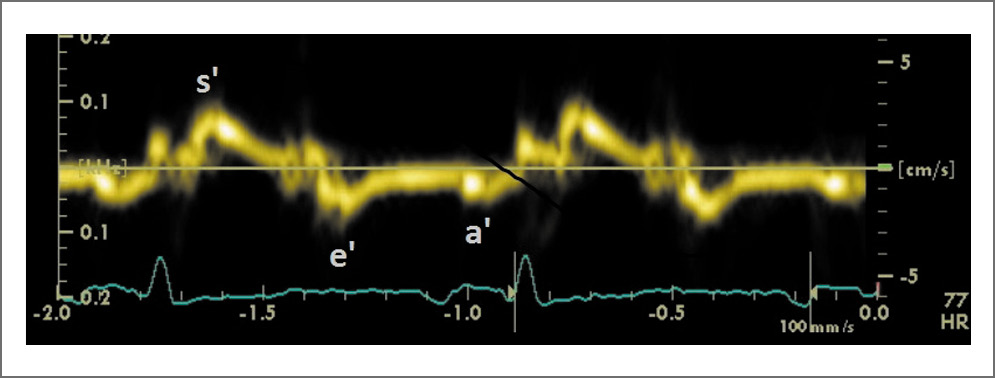

Рис. 4. Тканевая допплерограмма латеральной части митрального кольца (s’, e’, a’ – скорости движения кольца митрального клапана в фазы систолы ЛЖ, раннего наполнения ЛЖ и систолы предсердий соответственно)

- выраженная диастолическая дисфункция ЛЖ: рестриктивный тип наполнения ЛЖ (повышено конечно-диастолическое давление ЛЖ), Е/e’=35; максимальная скорость трикуспидальной регургитации 3,2 м/с (см. рис. 3, 4).

Резко снижена систолическая скорость движения кольца митрального клапана, низкие показатели деформации ЛЖ (средний 2D-strain=-4,4%, в большей степени нарушение кинетики задней, боковой и передней стенок ЛЖ, в меньшей степени снижены показатели деформации верхушки ЛЖ). Систолическая дисфункция ПЖ: TAPSE – 16 мм, TAVS – 7–8 см/с.